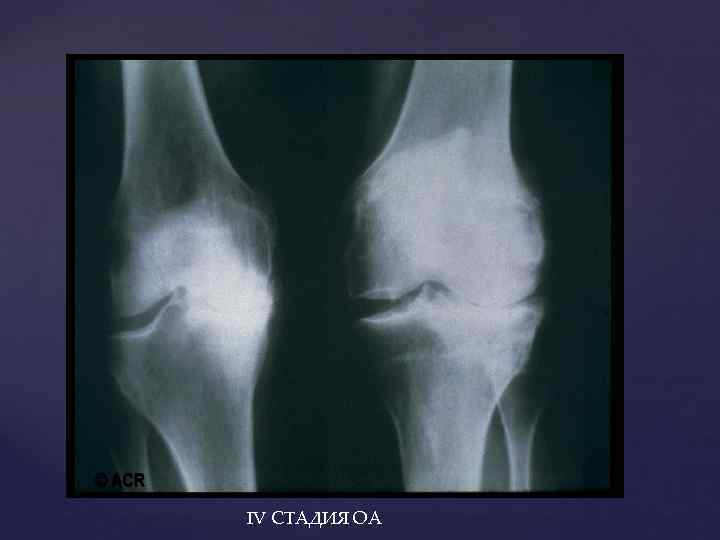

IV СТАДИЯ ОА

IV СТАДИЯ ОА